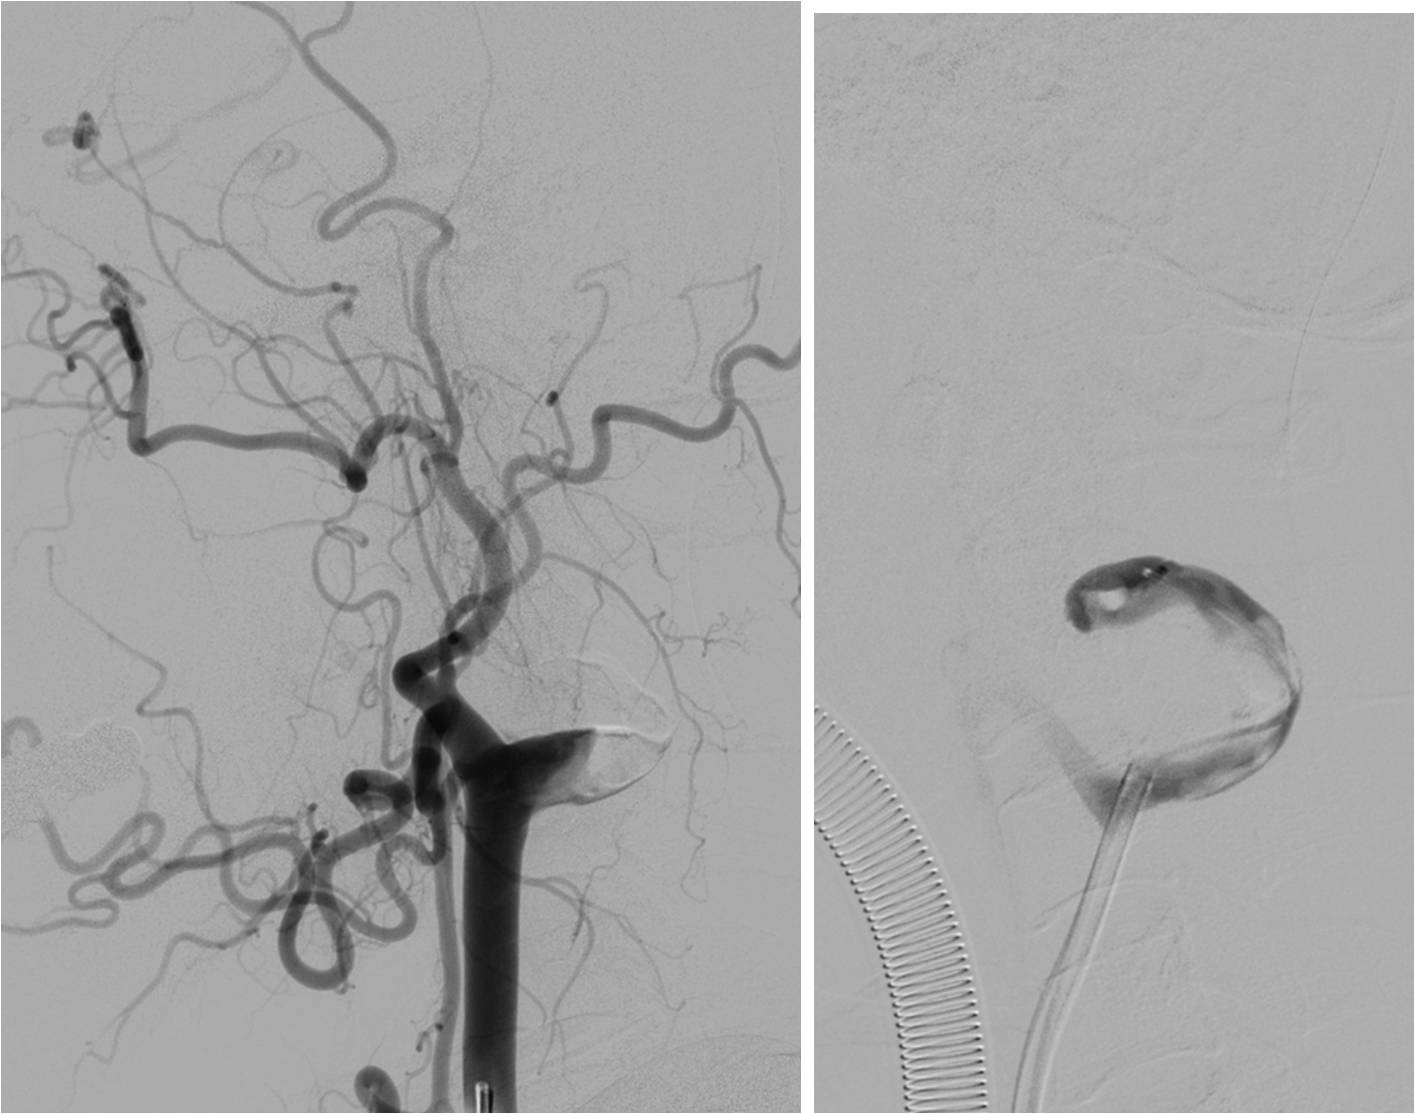

》男性,43岁,头痛、头晕伴发作性意识不清10余天入院。脑电图异常,查体无阳性体征。入院诊断“病毒性脑炎”。

》入院第3天,突发混合型失语伴右侧肢体活动不灵。

》头MRI+MRA:左侧岛叶斑片状异常信号,左侧颈内动脉不显影,左侧大脑中动脉显影较淡,远端分支较少。

》重点脑血管造影

》全麻下手术